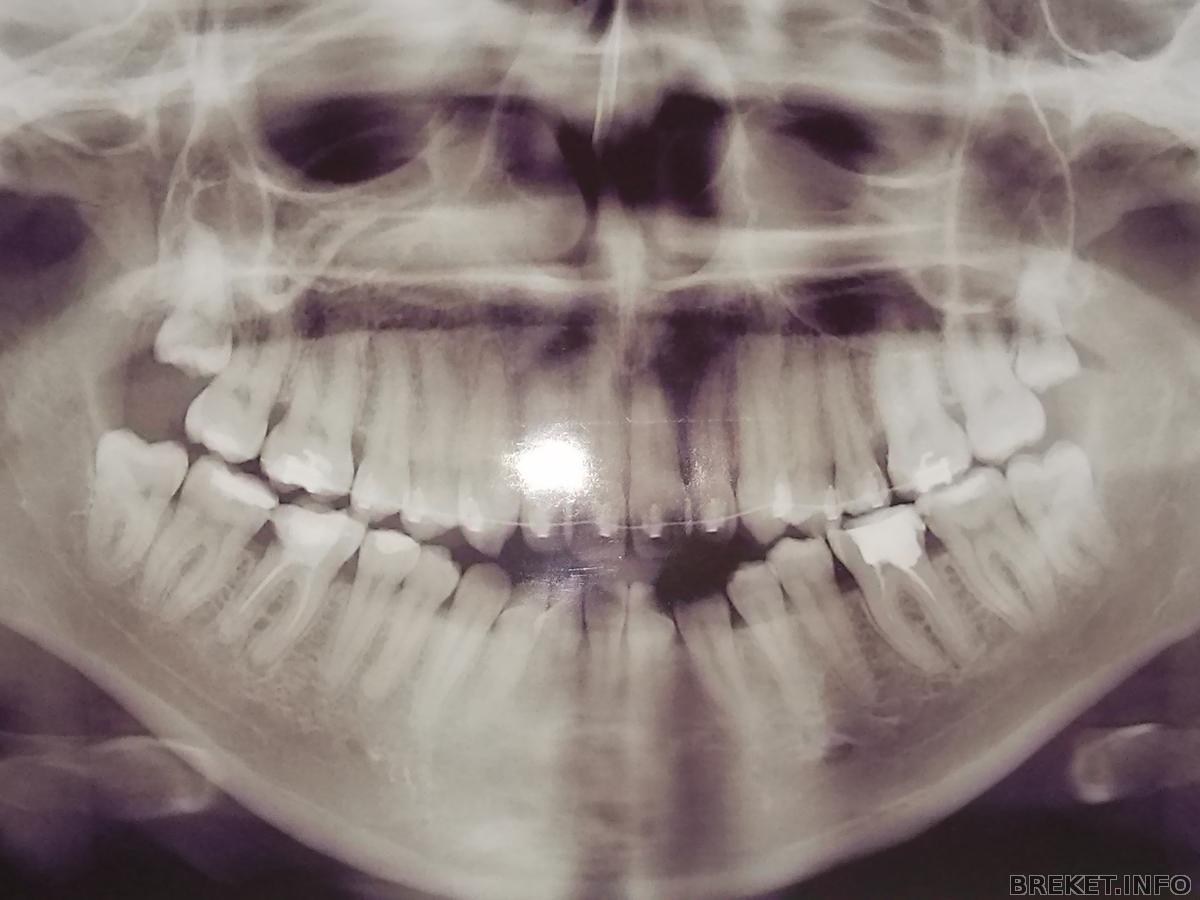

EVGENIYA., движение очень даже неплохое, двоечка молодчинка. А вам сепарация предстоит?? А что на снимке?? Я снизу слева одно что 9 зубов насчитываю, или это двойка такая суперширокая, хотя на фото это не заметно???

Annachka45 по-моему у Евгении центр смещен, поэтому на снимке так показалось

Annachka45 Сепарацию даже не обсуждали. На снимке верхние ретинированные 8ки (в альбоме описание было, не совсем разобралась, что к чему тут). Не пойму зачем их оставлять, чего сразу не удалить.. Хирург сказал, что они сами не вырастут, так как для них просто нет места и необходимости вырывать нет. Только если ортодонт даст команду. Ортодонт тоже говорит, что вырывать пока не надо.. А как же драгоценное место под ровные зубы?!. Ничего не поняла...

Нижние 8ки вырвали сразу.. и их там 8 было

на снимке и правда на 9похоже, двойка раздвоилась

испугалась,пересчитала - 7 порядок ))